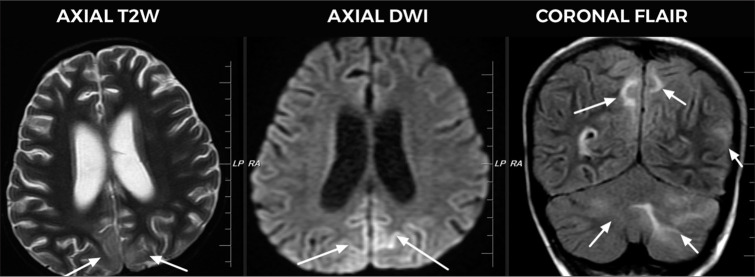

本研究描述了在儿科血液肿瘤科确诊的后可逆性脑病综合征(PRES)患儿的概况,并强调了免疫抑制儿童 PRES 的临床特征。这项回顾性研究纳入了10名被诊断患有PRES的儿童,他们的平均年龄为6.8岁。急性淋巴细胞白血病是最常见的主要诊断,其次是造血干细胞移植后患者。大多数PRES病例发生在开始治疗的一个月内。所有患者在确诊时都患有高血压。神经影像学检查发现双侧病变,顶叶和枕叶受累最为常见。所有患者在初诊时都接受了皮质类固醇治疗。控制血压是治疗 PRES 的关键。在儿科血液肿瘤科,如果儿童出现头痛、癫痫发作和视力障碍等症状,考虑到PRES的临床可能性,将有助于在排除引起这些症状的其他原因后进行早期诊断。

This study describes the profile of children diagnosed with posterior reversible encephalopathy syndrome (PRES) in the pediatric hematology oncology unit and highlights the clinical features of PRES in immunosuppressed children. This retrospective study included 10 children diagnosed with PRES with a mean age of 6.8 years. Acute lymphoblastic leukemia was the most common primary diagnosis followed by post-hematopoietic stem cell transplant patients. Most cases of PRES occurred within one month of treatment initiation. Hypertension was noted in all at the time of diagnosis. Neuroimaging revealed bilateral lesions with parietal and occipital lobe involvement being the most common. All patients received corticosteroids as part of treatment for primary diagnosis. Controlling blood pressure was critical in managing PRES. Consideration of PRES as a clinical possibility in pediatric hematology oncology unit in children presenting with symptoms such as headache, seizures, and visual disturbances will aid in early diagnosis after ruling out other causes of these symptoms.